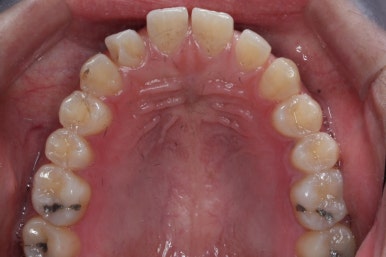

위 사진은 부산치아교정치과에 내원하셨을 대 당시의 입안 모습입니다.

치아들 사이에 전반적으로 틈이 많이 있는 상태입니다.

전반적으로 흩어져 있던 틈새를 특정 위치로 모으기 시작합니다.

앞니 사이의 틈을 제일 보기 싫어하실 것 같으므로 앞니 부터 빠르게 틈을 보아줍니다. 대신 작은 어금니 부위로 틈을 모으는 작업을 하게 됩니다.

서서히 틈이 줄어들고 있는 것이 보입니다.

벌써 몇 군데는 틈이 다 모였습니다.

이제 거의 다 끝나가고 조금 더 마무리하면 됩니다.